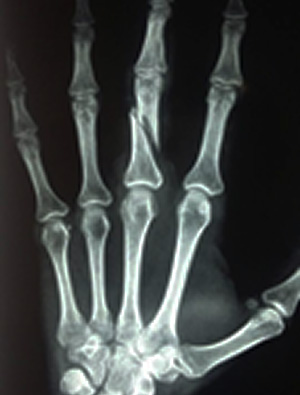

(Foto: Divulgação/Secretaria de Saúde de Sinop)

Segundo o secretário municipal de saúde, Manoelito Rodrigues, a médica teve o dedo médio fraturado e deve passar por uma cirurgia.